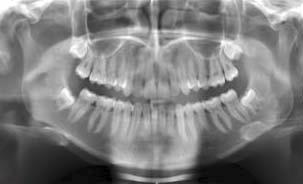

If your wisdom teeth are not visible, a full mouth x-ray (OPG) is used to assess the presence and position of these teeth. Your dentist can arrange for the x-ray to be done.

Wisdom teeth can grow in a variety of positions. A number of factors will determine whether your wisdom teeth will come through in a favourable position. These include the size of your teeth, the space available in the jaw, the position and angle of the wisdom teeth when they are developing. Your dentist will assess the position and angle of the wisdom teeth on your x-ray and can recommend the appropriate management of these teeth. When there is not enough room for the wisdom teeth to come through, they can become wedged or ‘impacted’.